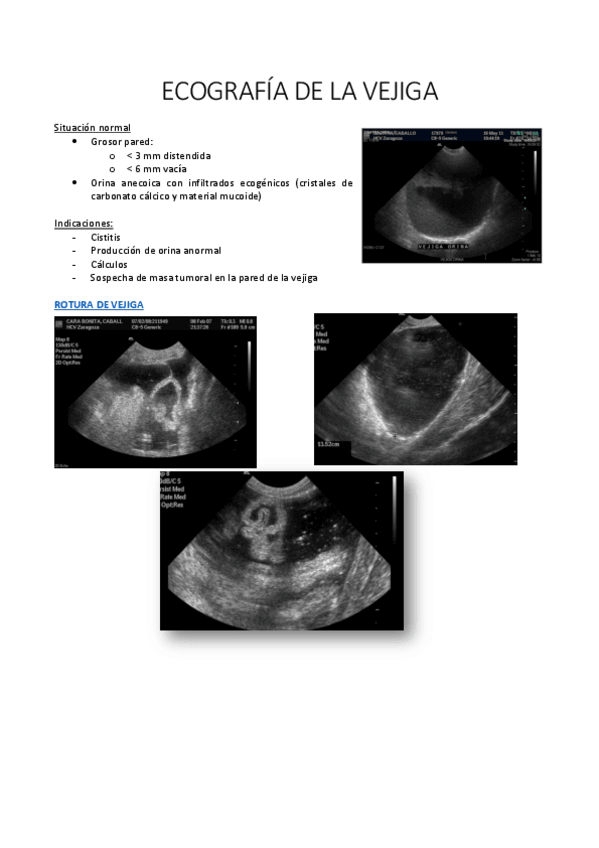

ECOGRAFIA-DE-LA-VEJIGA.pdf